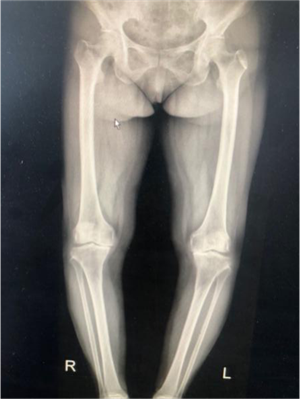

?。ㄊ中g前、手術后對比)

5月29日,徐阿姨如期進行了雙側(cè)全膝關節(jié)同期置換術。術中發(fā)現(xiàn)徐阿姨膝關節(jié)退變嚴重,有大量的滑膜軟骨瘤,清除病變后又發(fā)現(xiàn)她前交叉韌帶缺失后交叉韌帶纖細,即決定采用限制性較高的E1 AS墊片,該假體極大的提高了手術安全性,降低了手術風險和創(chuàng)傷,手術歷時2小時,患者術后恢復良好。手術后第二天,徐阿姨就可以扶著助步器下地活動,目前已可以徒步行走、上下樓梯。